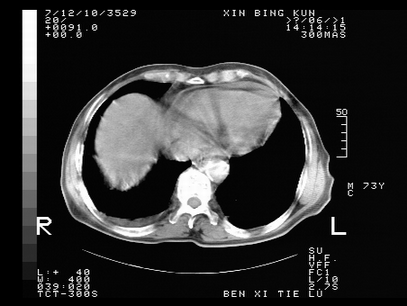

标题: CT10820:男,73岁,病史肺TB,现病史肺炎,直肠CA术后 [打印本页]

标题: CT10820:男,73岁,病史肺TB,现病史肺炎,直肠CA术后

双肺间质改变,依据病史双肺多发结节灶考虑转移,少量胸水.

1.两肺结核.2.两肺多发转移瘤.3右侧少量胸腔积液4.主动脉钙化.

双肺多发结节及条片状致密影,右侧少量胸腔积液。临床:直肠ca术后,肺tb病史。综合考虑:1 双肺转移!2 继发性肺结核合并感染!

此人病史较复杂,原有肺结核,直肠癌术后。肺部病灶形态亦呈多形性。因此,不可仅以一种病来解释肺部的病变。双肺多发的类圆形结节灶,结合病史还是首先考虑转移瘤,而双肺其余病灶还需结合化验室检查,结核或肺部感染在无其它检查资料的情况下不好排除。还是那句话----放射科医生不是开照像馆的,我们也是医生,看片一定要多结合临床及其它检查资料。要当一名合格的放射科医生,并不比当一名临床医生容易,我们可别把自已不当医生看。

两肺多发结节影,并见滋养动脉与其相连,考虑 两肺转移. 右侧胸腔积液考虑胸膜转移.

左肺上叶下叶背段,右肺中下叶见多发斑片状、条索状高密度影,兵变周围小结节影形成“树芽”样改变。 左肺上叶舌段近前胸壁处及右肺中叶内侧段见结节影。右侧胸膜腔内见液体密度区。纵隔内未见明确增大淋巴结。考虑左肺上叶舌段近前胸壁处及右肺中叶转移瘤可能性大。两肺继发型肺结核。右侧胸腔积液。